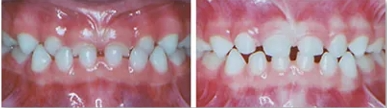

Children with moderate to severe dental crowding will benefit from interceptive or early orthodontic treatment. Parents typically notice crowding when the lower front permanent teeth first appear around age 6 years. At The Kids Place, our pediatric dental team will evaluate patients' smiles early on, when permanent teeth should be coming in, if they are crowded, when they are delayed, and when they are coming in out of position.

By recognizing and addressing orthodontic concerns early, we can often eliminate future extractions of permanent teeth, improve overall health and function of the mouth, and help give your child a beautiful smile.

Orthopedic arch development can often make room for the permanent teeth eliminating extensive treatment times later, and will reduce or eliminate the removal of permanent teeth that so often occurs when children undergo orthodontic treatment at a later age. In addition, arch development can improve your child's ability to breath, and breath through the nose. Nasal breathing is the key to a well balanced face.

In the traditional model of orthodontic care, braces are delivered after all or at least most of the permanent teeth are in the mouth. Thus, most kids get braces in their late childhood or early teen years. At this age the majority of facial growth (90%) has occurred and options to deal with crowded teeth have become more limited. Dental crowding, on the other hand, starts early with the eruption of the first permanent teeth around age 6 years.

Waiting years for treatment can lead to compromise in facial growth and esthetics, compromise in health, loss of permanent teeth, or even more extensive and expensive treatments. At The Kids Place, we focus on treating dental crowding early, when the face has a larger growth potential.

Gently guiding your child's dental arches back to normal dimensions will allow room for the permanent teeth to come in uncrowded, assist in correct muscle and tongue function, and even improve nasal breathing.